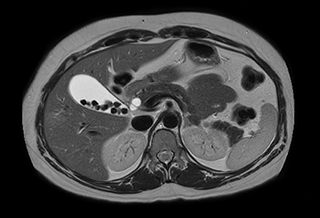

Ascites can be hard to image, but excellent result is obtained with Ingenia Ambition. This high resolution image demonstrates the high quality that can be obtained with VitalEye and the patient just breathing normally. The acquisition time is fast thanks to the accuracy of the respiratory gating with VitalEye** and it also saves the time needed to put a respiratory belt on the patient.

3D T2 with VitalEye

Performed on Ingenia Ambition. FOV 430 mm, voxels 1.3 x 1.3 x3.0 mm, 130 slices, Breath hold 16.6 sec

Using mDIXON provides excellent fat saturation uniformity. No artifacts seen at the edges in these images, while these were quite commonly seen with eTHRIVE on our previous system. Note also the high resolution.